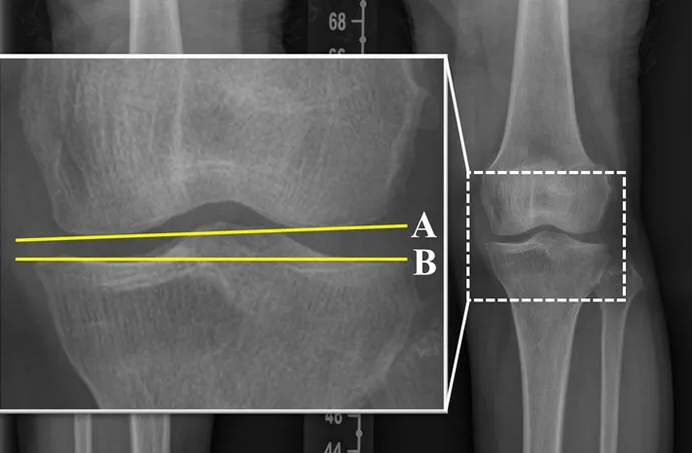

¹«¸­ ÅðÇ༺ °üÀý¿° ¼ö¼ú ÈÄ °¢µµ °ü¸®, ¾çÃø ¹«¸­ °Ç°­¿¡ Áß¿ä

ÃÖ±Ù ¿¬±¸¿¡ µû¸£¸é, ÈØ ´Ù¸®¸¦ ±³Á¤ÇÏ´Â ¼ö¼úÀ» ¹ÞÀº ȯÀÚ¿¡¼­ °üÀýÀÇ °¢µµ°¡ ÀûÁ¤ ¹üÀ§¸¦ ¹þ¾î³ª¸é ¼ö¼úÇÑ ¹«¸­»Ó¸¸ ¾Æ´Ï¶ó ¹Ý´ëÂÊ ¹«¸­¿¡µµ ÅðÇ༺ °üÀý¿°ÀÌ ¹ß»ýÇÒ À§Çè..